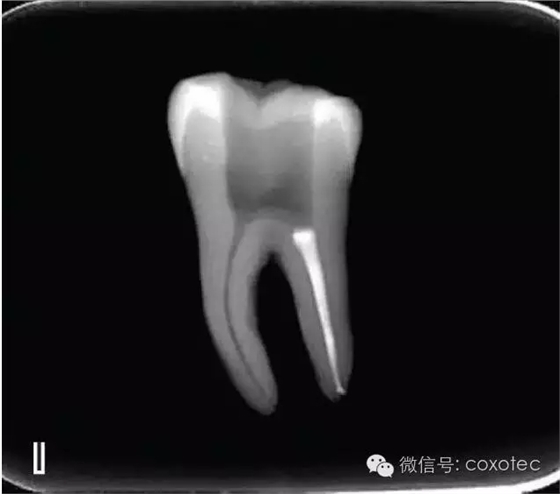

圖7 退出攜熱器工作尖,A.垂直加壓器加壓 B.根尖段的充填完成 在完成根尖段的充填后,使用熱塑牙膠注射儀對根管中上段進行分層充填,一般分2~3次完成充填,每次充填均使用相應直徑大小的垂直加壓器進行加壓。拍片確認充填效果(圖8)。

A、B.注射儀注射中段熱牙膠

C、D.垂直加壓器加壓

E、F.注射儀繼續(xù)注射上段熱牙膠

G、H.垂直加壓器加壓

I、J.完成根中上段的充填